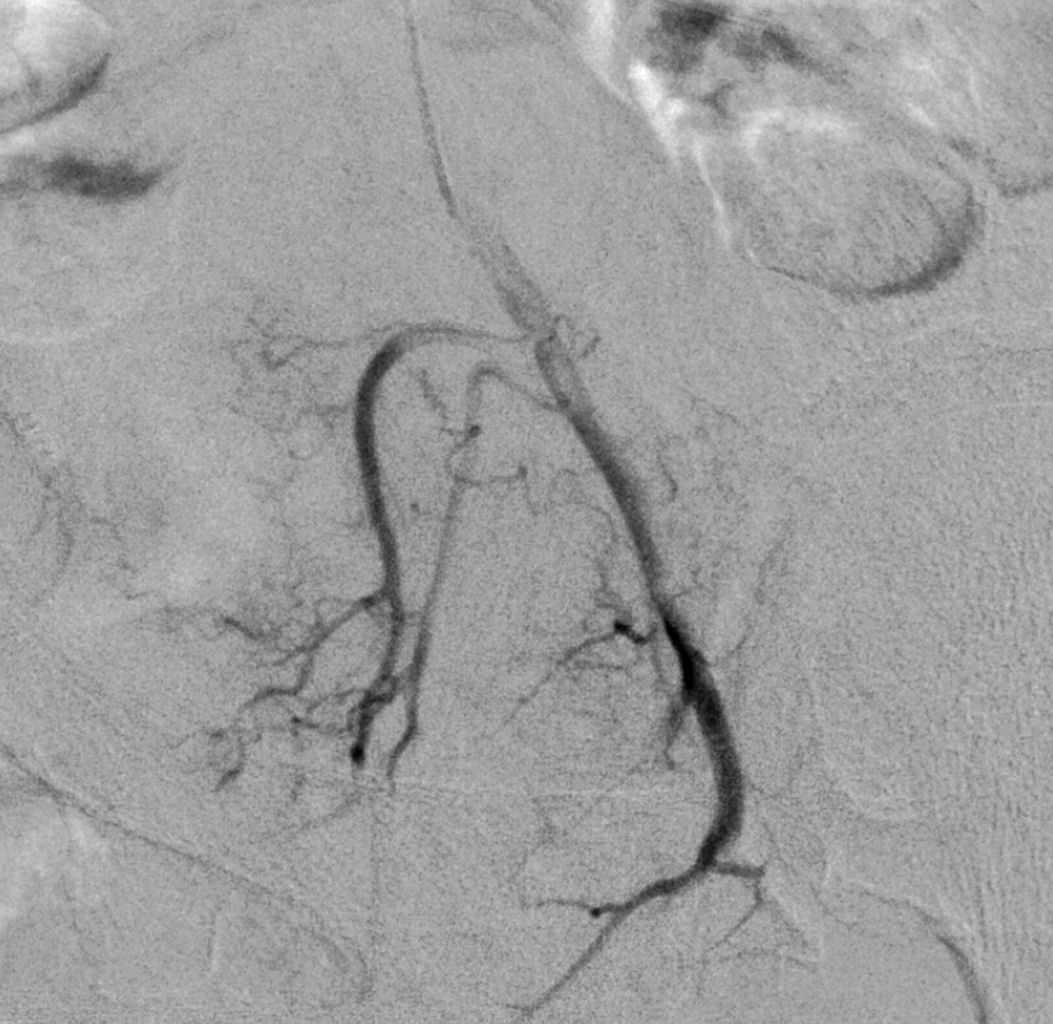

Die tumorversorgenden Lebergefäße werden selektiv mit einem Katheter aufgesucht.

Der Tumor wird selektiv mit einem Mikrokatheter ausgesucht und lokal chemoperfundiert.